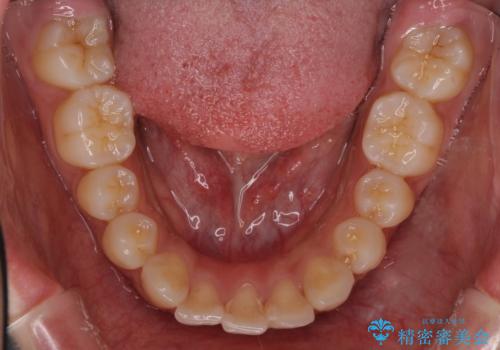

口元の突出感がありと、下顎の前歯が1本欠損していました。

上顎の前から両側の前から4番目の歯と、下あごの前歯を1本抜歯して、口元をすっきりさせる計画としました。